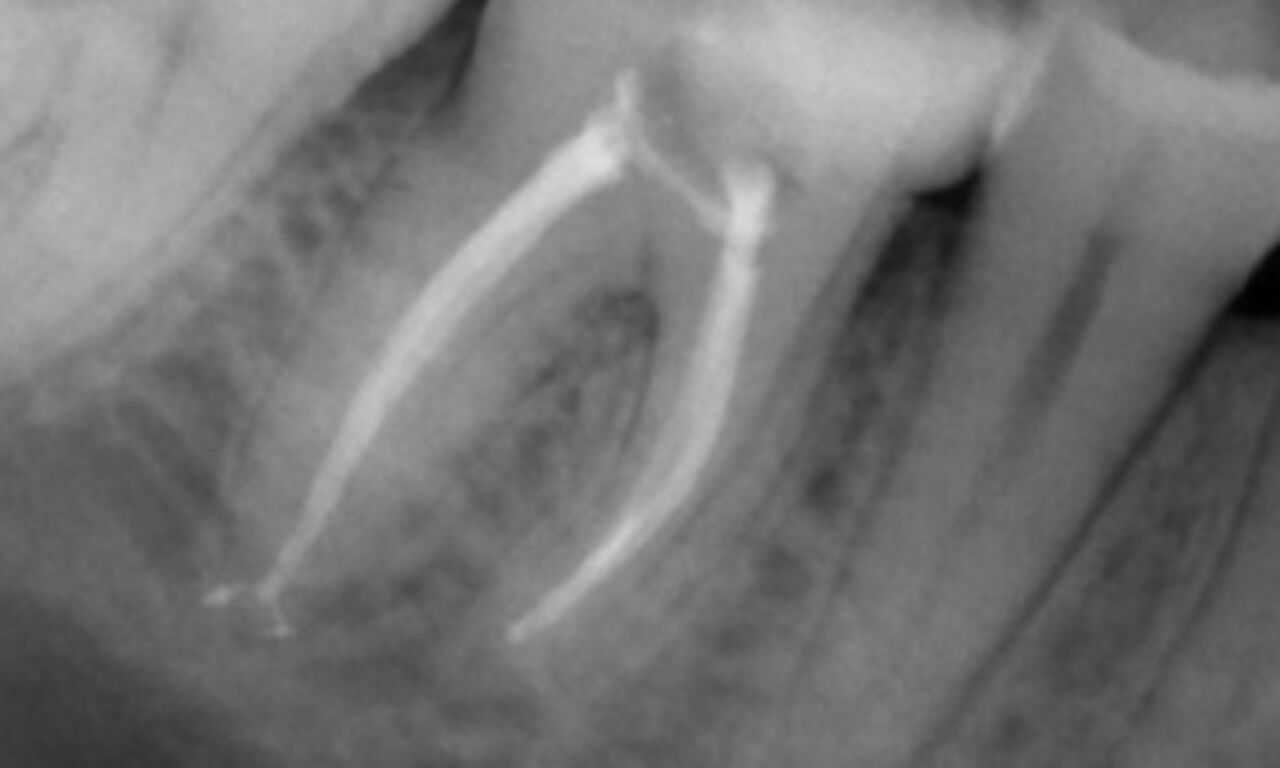

Periapical radiolucency associated primarily with the distal root and loss of lamina dura on the mesial root.

TruNatomy was chosen in this case to allow a caries leveraged approach and a focus on pericervical dentin preservation especially on the mesial aspect where the tooth had a more minimal restoration.